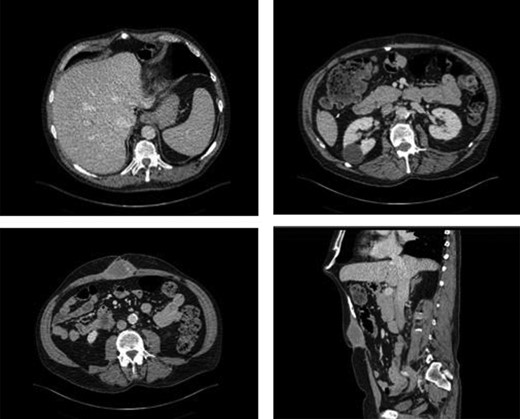

A 65 year-old male was suffering from chronic abdominal pain and foreign body sensation following incisional hernia repair with mesh in 2010. In March 2010, the patient underwent an open right hemicolectomy for benign multiple colonic polyps and subsequently developed an incisional hernia. In November 2010, he underwent open incisional hernia repair with an onlay Prolene mesh. Subsequent to the mesh repair, he had sharp pain in the epigastric area particularly when bending forward and fullness in his upper abdominal region. He was referred to the outpatient general surgery clinic at a tertiary level hospital for an assessment. On focused abdominal exam, he had a midline laparotomy incision with no acute signs of infection. There was fullness superior to his umbilicus with a palpable subcutaneous mass measuring approximately 6 cm in diameter. Cross sectional imaging revealed an ovoid collection in the anterior abdominal wall, measuring 4.4 × 8 cm on magnetic resonance imaging (MRI) and 3.3 × 5.4 cm on computed tomography (CT). In addition, an abnormal calcification superior to the collection could be appreciated on CT (Fig. 1). These findings were suggestive of a chronic hematoma and scar tissue. The patient agreed to undergo debridement of chronic hematoma and partial mesh excision. Intraoperatively, the ovoid collection was approached via a midline incision and was encountered after dissection through the subcutaneous tissue. It was comprised of a thick rind of scar and fibrous tissue, measuring approximately 8 × 8 cm. It was unroofed, with immediate expression of old hematoma as well as fibrous tissue. Part of the overlying Prolene mesh and thick scar tissue were excised. The remainder of the Prolene mesh was well incorporated to his fascia and left in place. As the superior aspect of the collection was dissected out by entering deep to the fascia, a piece of calcified tissue was dissected out from the preperitoneal space superior to the mesh. It was suspected to be heterotopic ossification, and it was removed (Fig. 2). The fascia was then primarily repaired, and then the incision was closed in layers after thorough irrigation. On postoperative follow-ups in the clinic at 2 and 6 weeks, the patient was doing well, and his pain had improved significantly.

CT of the abdomen demonstrating anterior abdominal wall collection and the abnormal calcification. It revealed an ovoid collection within the anterior abdominal wall in the midline inferior to the mesh measuring 3.3 × 5.1 × 5.4 cm. In addition, it showed the abnormal calcification below the xiphoid process.